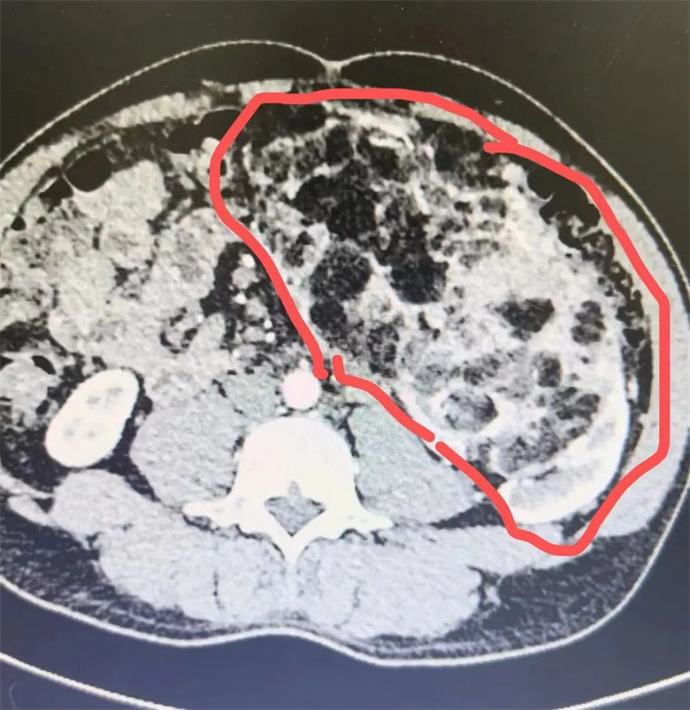

近日,我院泌尿外科會診一位四十多歲男性患者時發現,該患者腹部有一巨大腫瘤,直徑近30cm,已將該患者胃、胰腺、脾臟及部分腸管擠壓移位,且腫瘤內可見大量動靜脈畸形,存在極大的出血風險,一旦出血將危及患者生命,客觀告知患者及家屬相關病情后,患者及家屬憂心忡忡,基本的日常活動都心有畏懼,充分溝通后,轉入泌尿外科,擬行手術治療。

轉入泌尿外科后,強永春主任及專家組積極術前準備,仔細閱片,充分討論,明確此腫瘤來源為左側腎臟,多考慮為腎臟血管平滑肌脂肪瘤,俗稱“錯構瘤”。周莉護士長帶領護理組通過傾聽、解釋、鼓勵、提供支持、建立信任等來安撫患者的憂心忡忡,幫助他們更好地應對疾病。科學、客觀的指導患者的術后康復。

錯構瘤屬于良性腫瘤,絕大多數錯構瘤患者沒有明顯的癥狀,一些比較大的錯構瘤,可能會出現局部壓迫癥狀或壓迫周圍臟器,出現相應的癥狀。腎錯構瘤最大的危害在于,體積較大的錯構瘤突然破裂時,患者會出現腰腹疼痛和血尿等癥狀,嚴重的大出血患者可以在腹部觸及到包塊,甚至有休克癥狀。因此當腫瘤直徑大于4cm時,一般會積極建議手術,減少自發破裂的風險。但該患者平素未行體檢,腫瘤已近30cm,因此貿然手術處理存在巨大的風險。

強永春主任帶領泌尿外科團隊積極協調,提前預約腫瘤介入王忠主任,于術前行介入栓塞,減少術中出血風險;同時聯系輸血科提前術中備血;因腫瘤已侵及腎臟大部及腎臟血管,無法保留腎單位行腎部分切除,故先側臥位行后腹腔鏡下微創手術,游離并處理腎臟血管,確保切除時安全,再仰臥位行錯構瘤及腎臟切除;充分準備后,手術按預定方案如期進行,歷時6小時,成功拆除“定時炸彈”。目前患者已出院恢復了日常工作。